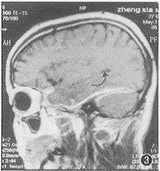

图3 1998年5月MRI矢状位增强示颞叶水肿,↑示右侧脑室颞角受压变小。HCP累及中颅窝底脑膜及小脑幕

图4 1998年5月MRI横断面增强扫描示HCP包绕右颞叶下极。颞叶水肿。病变累及右侧海绵窦。↑示颈内动脉颅内段变小。小脑幕受累增厚,明显强化

出院7个月后,1998年4月,出现精神异常,时而安静,时而烦躁打骂亲人,曾送精神病院治疗未见好转。1998年5月13日来院复查。除精神症状外,一般情况良好。MRI颅脑横断面、冠状及矢状位扫描并增强显示:右中颅窝底硬脑膜、右侧小脑幕均见明显强化的带状影,右侧颞叶水肿,局部脑沟消失(图2);右侧脑室颞角受压变小(图3);右侧海绵窦影明显增大,增厚的窦壁使颈内动脉受压变细(图4)。根据MRI所见及临床症状确诊为弥漫性肥厚性硬脑膜炎伴右颞叶水肿及器质性精神障碍。每天青霉素静脉点滴10 000 000 U共26 d,临床症状消失。1999年8月28日(15个月后)复查 MRI,颞叶水肿消退,沟回重现,侧脑室颞角恢复正常(图5),肥厚的硬脑膜因已纤维化,故不再强化,但右侧颈内动脉仍受压(图6),2000年4月(23个月后)电话询问,患者工作、生活良好,并已成婚。